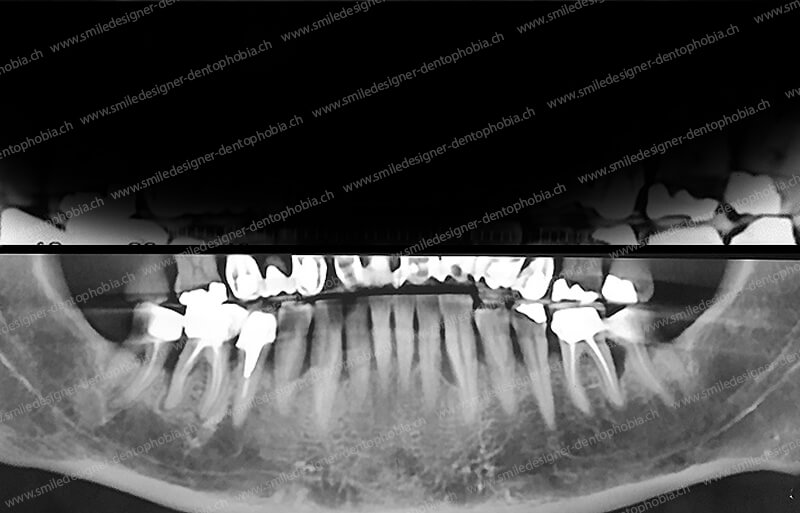

Cas clinique « DAMAGE CONTROL MCI » mandibulaire : Bridge implanto-porté avec extensions postérieures (ALL ON 8). Version définitive du bridge avec un cosmétique en céramique.